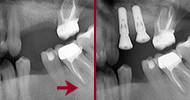

bavi se zamjenom izgubljenog prirodnog zuba umetanjem zubnog implantata unutar kosti donje ili gornje čeljusti

protetski radovi nadomještavaju jedan ili više zubi koji nedostaju, obnavljajući njihovu funkciju i estetiku.